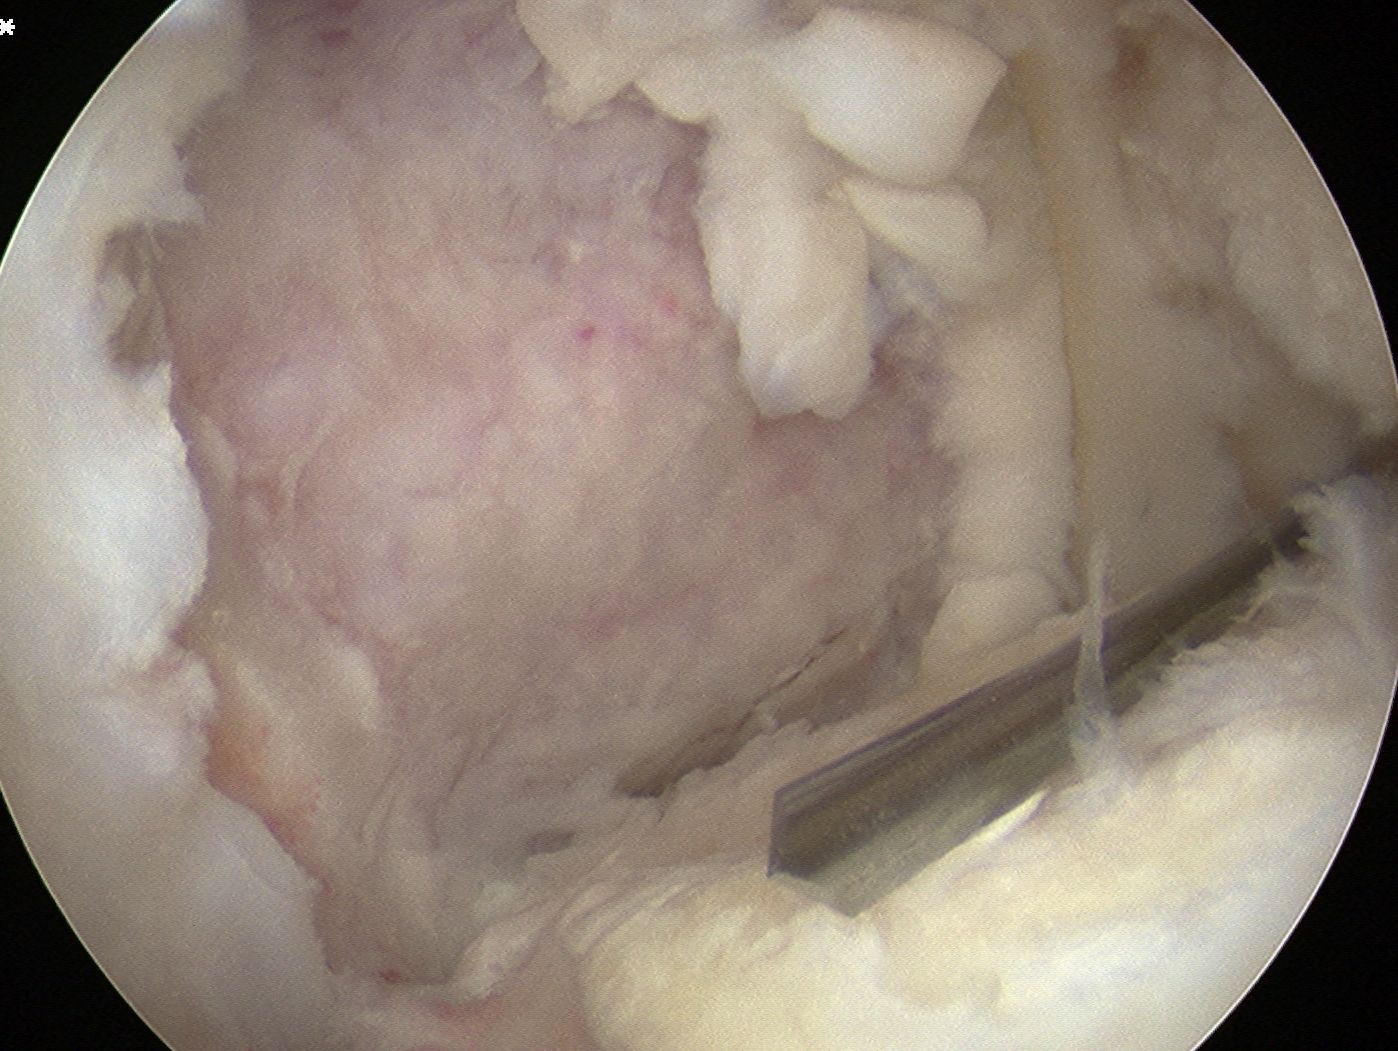

Debride base of lesion

Fibrous tissue removed meticulously from femur with curette and shaver